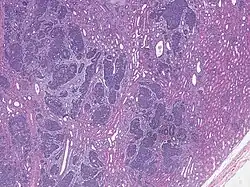

High magnification micrograph showing the three elements of Wilms' tumor. H&E stain.

Low magnification micrograph of a Wilms' tumor infiltrating the renal parenchyma. It shows the characteristic triphasic pattern consisting of tubules, solid sheets of small round cells, and stroma. H&E stain. The surrounding renal parenchyma is more eosinophilic (pink) than the rather grey tumor stroma.

Pathologically, a triphasic nephroblastoma comprises three elements:[11]

Wilms' tumor is a malignant tumor containing metanephric blastema, stromal and epithelial derivatives. Characteristic is the presence of abortive tubules and glomeruli surrounded by a spindled cell stroma. The stroma may include striated muscle, cartilage, bone, fat tissue, and fibrous tissue. Dysfunction is caused when the tumor compresses the normal kidney parenchyma.